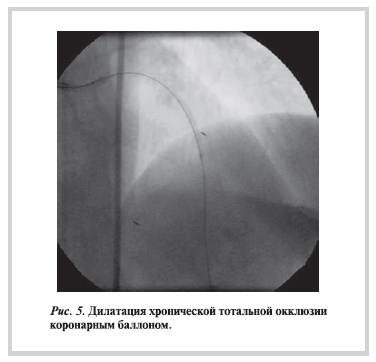

Рисунок 2. Раздувание коронарного баллона в хронической тотальной окклюзии.

После этого в ХТО был успешно заведен коронарный баллон и выполнена дилатация поражения (рис. 5).